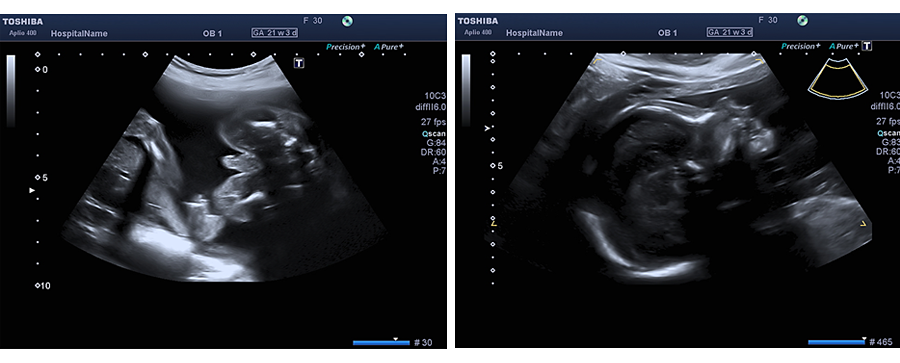

In der Zeit von der vollendeten 19. bis zur vollendeten 22. Schwangerschaftswoche kann das ungeborene Kind sehr viel detaillierter und umfangreicher als in dem von den Mutterschaftsrichtlinien vorgesehenen Ultraschall untersucht werden.

Bei dieser Ultraschalluntersuchung werden alle einsehbaren Organe des Kindes detailliert beurteilt sowohl in Hinblick auf Ihre korrekte Ausbildung als auch auf ihre korrekte zeitliche Entwicklung. Eine besonders wichtige Stellung nimmt hierbei die Beurteilung der Entwicklung und Funktion des kindlichen Herzens (Echokardiographie) ein. Des weiteren wird die Fruchtwassermenge, sowie die Lage und das Aussehen des kindlichen Mutterkuchens beurteilt.

Bei sachgerecht durchgeführter Untersuchung können also im Rahmen dieser „Feindiagnostik“ Fehlentwicklungen und Fehlbildungen ungeborener Kinder aufgedeckt werden und ggf. schon frühzeitig im Mutterleib therapiert werden (z.B. bei Herzrhytmusstörungen, einigen Infektionen etc.), Entscheidungen über eine eventuell notwendige nachgeburtliche Therapie (Operation eines Herzfehlers oder einer angeborenen Lippen-Kiefer-Gaumenspalte) getroffen werden, der Geburtsmodus (Kaiserschnitt oder Spontangeburt) und auch die Entbindungsklinik (ggf. Klinik mit angegliederter Kinderklinik) festgelegt werden.

Auch können bei dieser Untersuchung ähnlich wie beim First-Trimester-Screening so genannte Marker auffallen, die an sich keine Fehlbildung darstellen, und keinerlei Einfluss auf die Entwicklung der betroffenen Organe und damit des Kindes zeigen, welche jedoch das Risiko für das Vorhanden einer Chromosomenstörung erhöhen. Zu diesen Markern gehören im zweiten Drittel der Schwangerschaft zum Beispiel eine Verkürzung der Oberschenkel und Oberarme, eine Verbreiterung der Nierenbecken, Auffälligkeiten im Bereich des Magen-Darm-Kanals etc.

Diese detaillierte Ultraschalluntersuchung kann natürlich auch zu jedem späteren Zeitpunkt der Schwangerschaft durchgeführt werden, ist jedoch in der 19. - 22. Schwangerschaftswoche am aussagekräftigsten.